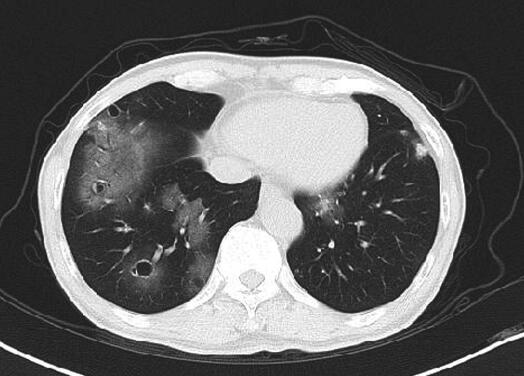

现病史:患者2014年9月在戴有强烈油漆气味义齿约10天后出现咯血,初始为痰中带少量鲜红色血液,2~3口/日,未给予重视,后痰中带血量逐渐增多至5~6口/日,且血量与痰量相当,偶感咽痒,无发热、牙周肿痛、乏力、盗汗,无胸痛、呼吸困难、喘息,偶有反酸,无恶心、呕吐、便血等,无皮疹、关节肿痛、肌痛、口眼干燥、反复发作口腔溃疡、光过敏等,一直未给予诊治。2014年10月25日觉咯血无好转就诊于社区医院,行胸部CT示“双肺散在大小不等的薄壁空腔样病灶,周围可见磨玻璃渗出影”(图1),后又于某三甲医院完善部分相关化验,但未明确病因,未给予治疗,10月28日为求进一步诊治入住我科。

图1 2014年10月25日胸部CT

双肺散在大小不等的薄壁空腔样病灶,周围可见磨玻璃渗出影